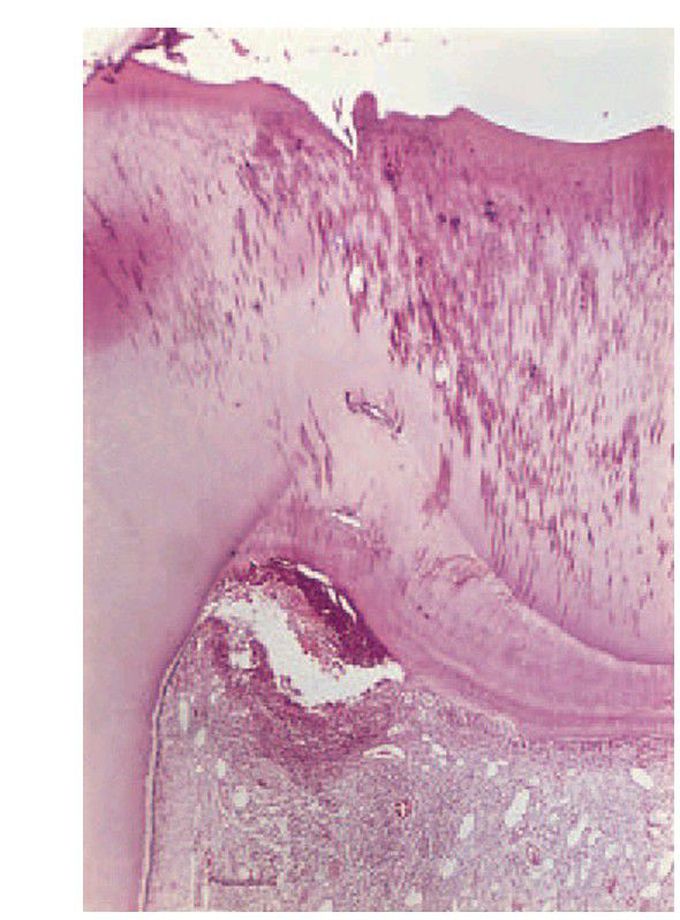

Acute pulpitis

. Infection has penetrated the reactionary dentine causing infl ammation to spread down the pulp and pus to form in the corner